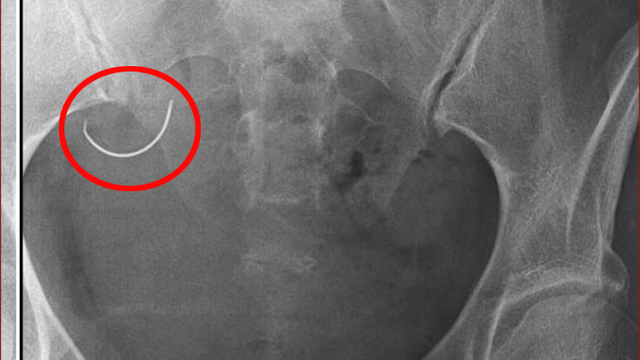

Operasyondan sonra Sabiha İ., şiddetli ağrılar yaşamaya başladı. Sabiha İ., ağrı nedeniyle tüp bebek tedavisi için gerekli ilaçları kullanamadı. Ü.İ., iddiaya göre bebek sahibi olamadıkları gerekçesiyle suçladığı eşine, 26 Mayıs 2024 tarihinde fiziksel ve psikolojik şiddet uyguladı. Sabiha İ. olaydan 1 gün sonra adli muayene için gittiği Kumluca Devlet Hastanesi'nde, karnında ameliyat iğnesi unutulduğunu, röntgen filmi sayesinde öğrendi. Doktorların sevk ettiği Antalya Eğitim ve Araştırma Hastanesi'nde yapılan ameliyat ile Sabiha İ.'nin karnındaki iğne alındı.